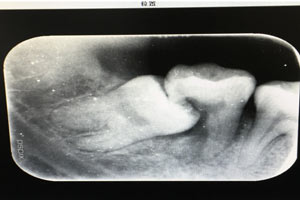

患者、申xx、女、40歲,主訴:左側(cè)下頜后牙牙齦紅腫不適數(shù)月。??茩z查:37合面有一開(kāi)髓孔。髓腔內(nèi)有一暫封小棉球,探針?biāo)枨坏撞砍鲅蔀樵谕庠褐委煂?dǎo)致底穿。x線片檢查:37頰側(cè)齦下有一枚多生牙,多生牙壓迫頰側(cè)牙根及牙體組織大量吸收。

圖2.術(shù)前的x線根尖片影像檢查:47遠(yuǎn)中牙根吸收。